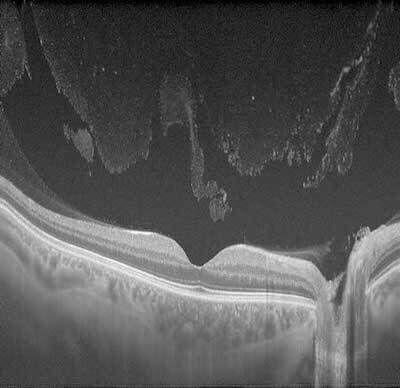

This is a cross section of the posterior part of the eye, taken with a machine called OCT (optical coherence tomography). The retina layers are nicely displayed in shades of grey. The vitreous, which is the fluid in the back part of the eye, is typically clear and represented as black on an OCT. When the vitreous cells clump together, they can be detected on OCT, and the patient sees “floaters”